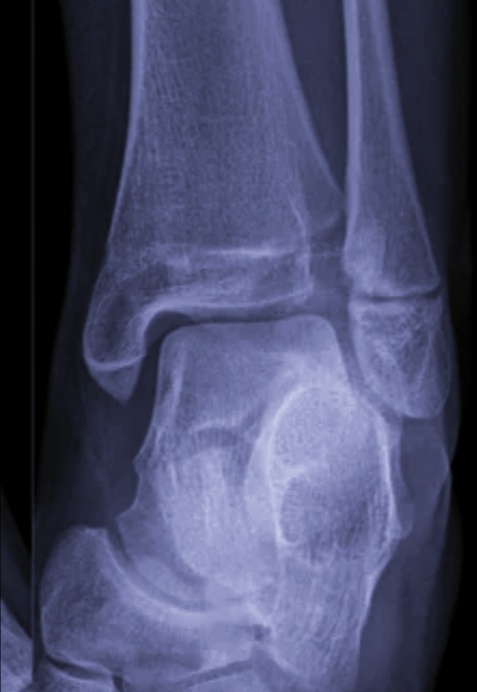

Он шел на своих двоих, ну, как шел, то спотыкался, то в сторону падал. Назначен снимок голеностопа.

Не вдруг, а самый настоящий!

-2

Обе сломал. Как только шел??